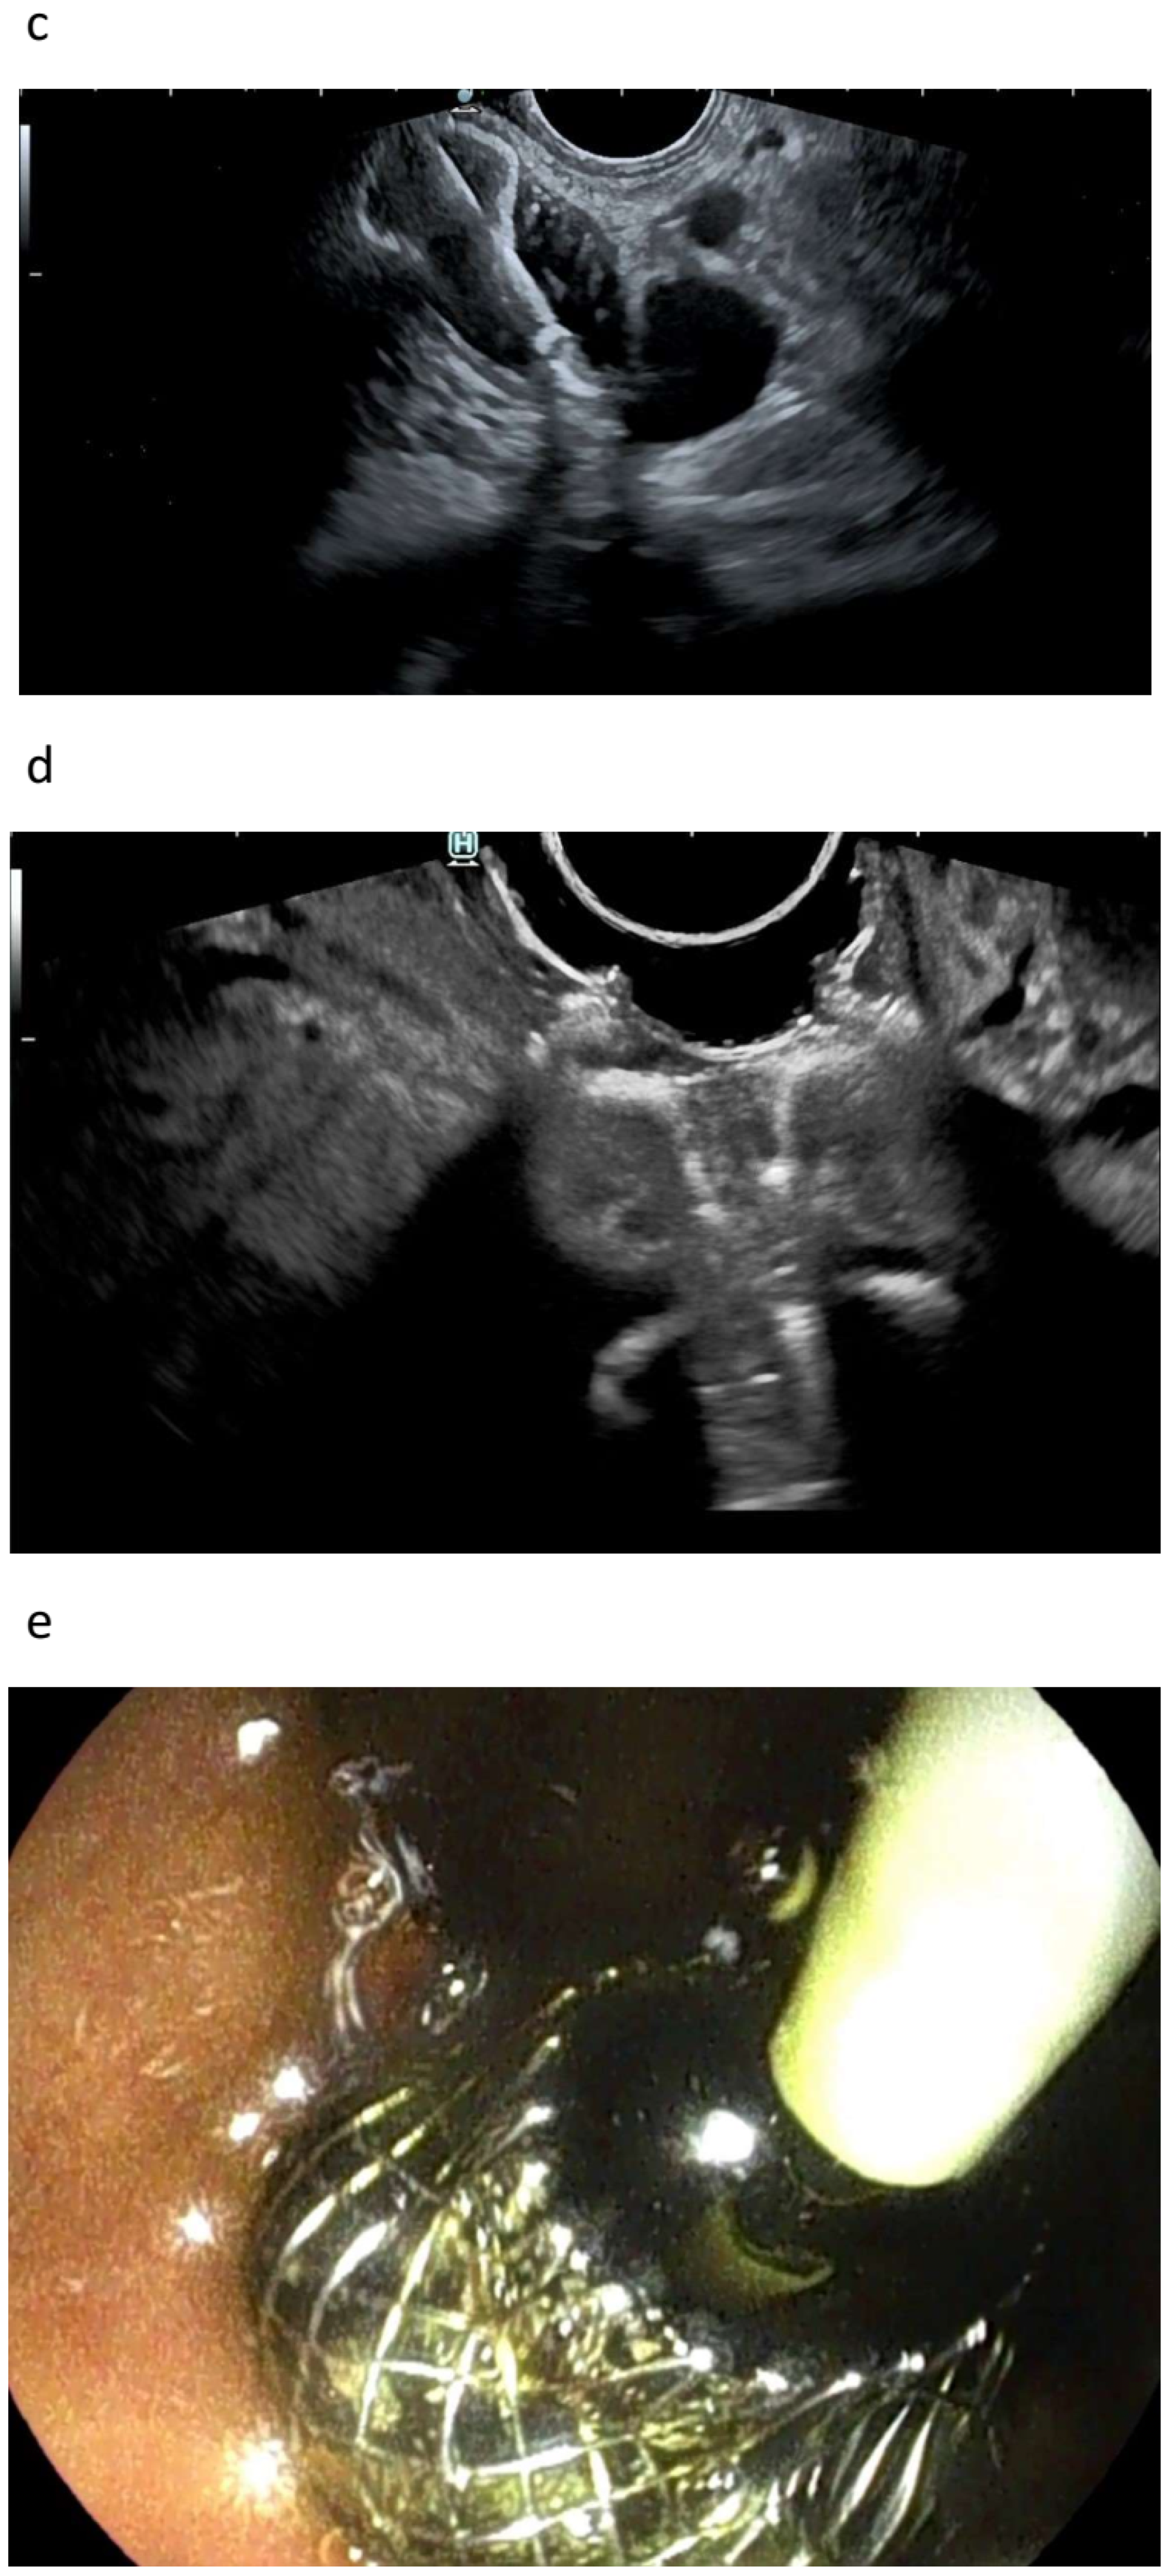

3.1.1. EUS-BD of the Bile Duct

3.1.2. EUS-GBD

3.2. Arguments against EUS-Guided Drainage